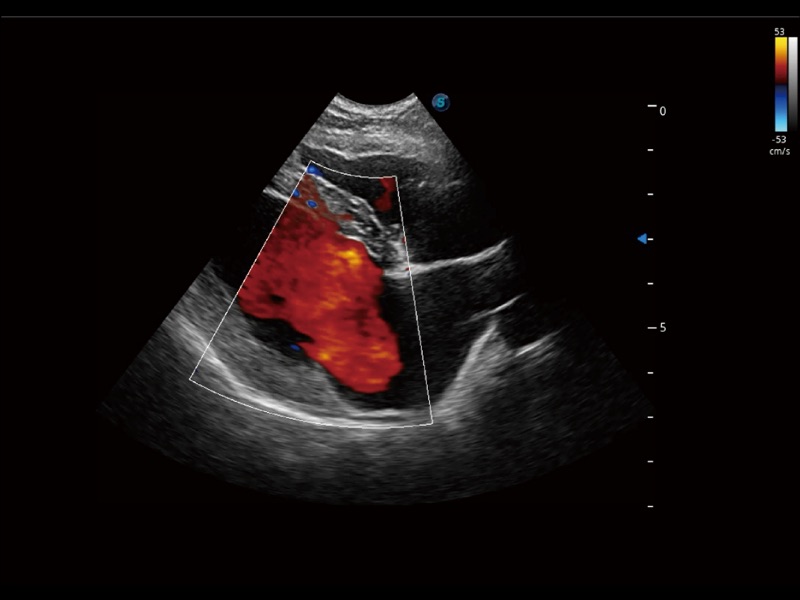

(犬)四腔心

• TDI 组织多普勒成像

实时用颜色表示心肌组织运动,观察和定量组织的运动情况,对快速检测与评估心肌的灌注和活性、电传导及心肌收缩和舒张功能等均能提供重要的诊断信息。